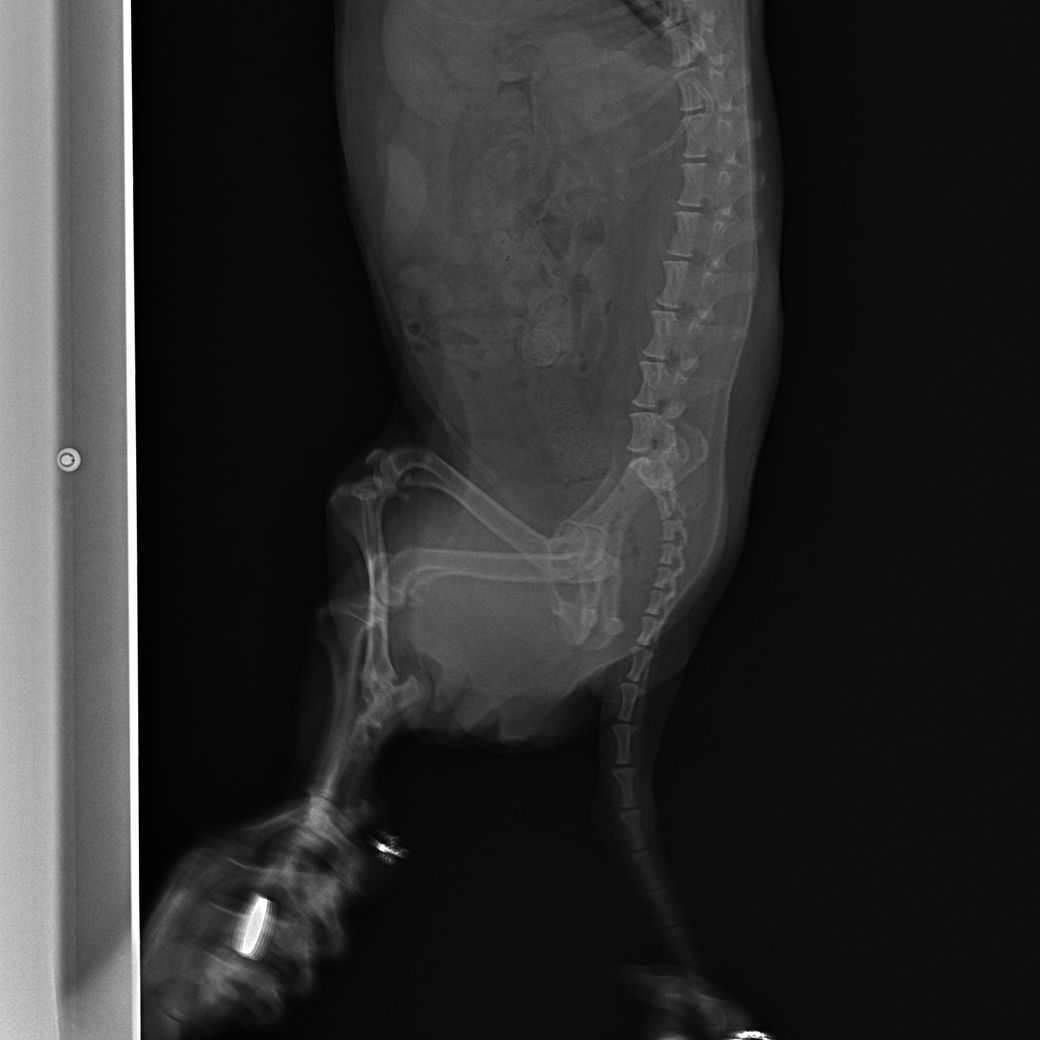

엑스레이만 봐서는 정확하게 진단을 내리긴 쉽지 않지만, 위내 고에코성의 물체가 보입니다.

그것이 내려가는지 여부 확인을 위해 주기적인 방사선촬영이나 위내시경이 필요해 보입니다.

폐 후엽 의 내측면에 종괴성 병변이 관찰되며 원발성 폐종양의 호발 부위로

1. 이부분의 압박으로 식도가 눌리기 때문에 음식물을 먹을때 통증을 호소할 수 있고

2. CT를 찍어 확인할 필요가 있으나, 원발성폐종양, 식도종양, 폐농양, 식도게실, 육아종성병변 등을 고려해야합니다. 이는 CT로 어느정도 감별가능합니다

3. 방사선상 종괴성 병변이 관찰 되는 상태이기 때문에 애니스캔도 높은 신뢰도를 갖습니다.

폐종양의 특징은 말기직전까지 "기침은 거의 하지 않습니다. 호흡도 괜찮습니다."라는 보호자의 병력이 특징적입니다. CT촬영 하시기 바랍니다.